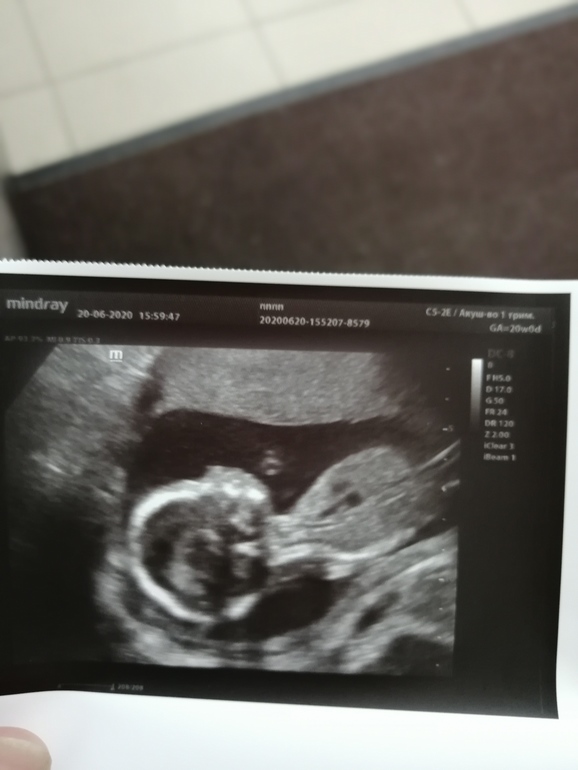

18+2 и второй скрининг ❤️+фото

Подтвердили нам пол, у нас будет маленькая принцесса ❤️❤️❤️

Сказали очень симпатичная курносая девчонка с большими глазами)

Малышка повернулась лицом и врач сфотографировала, как она улыбается 😍